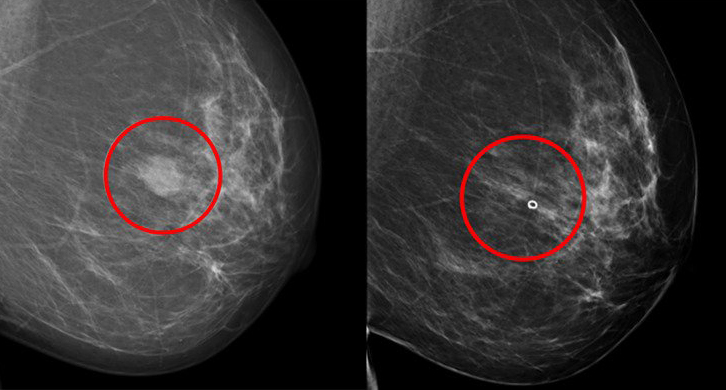

REDACCIÓN CIENCIA – Hoy en día, las posibilidades para determinar de antemano qué pacientes con cáncer de mama se beneficiarán de los distintos tratamientos son limitadas. Ahora, un equipo del Instituto Karolinska de Estocolmo ha desarrollado un método capaz de afinar en este sentido y de identificar los más adecuados.

El método que han desarrollado los investigadores del Karolinska se basa en aislar y cultivar no solo células tumorales, sino también las llamadas células de soporte de pacientes con cáncer de mama.

El estudio actual demuestra que es posible establecer este tipo de modelos tumorales celulares a partir de tumores de mama y que son similares a los tumores de origen de las pacientes en aspectos relevantes, por ejemplo genéticamente y en cuanto a diferentes marcadores proteicos.

Los modelos tumorales se crearon a partir de biopsias de 98 pacientes operadas de cáncer de mama, y en ellos se probaron más de 35 fármacos contra el cáncer de mama existentes y en fase de desarrollo.